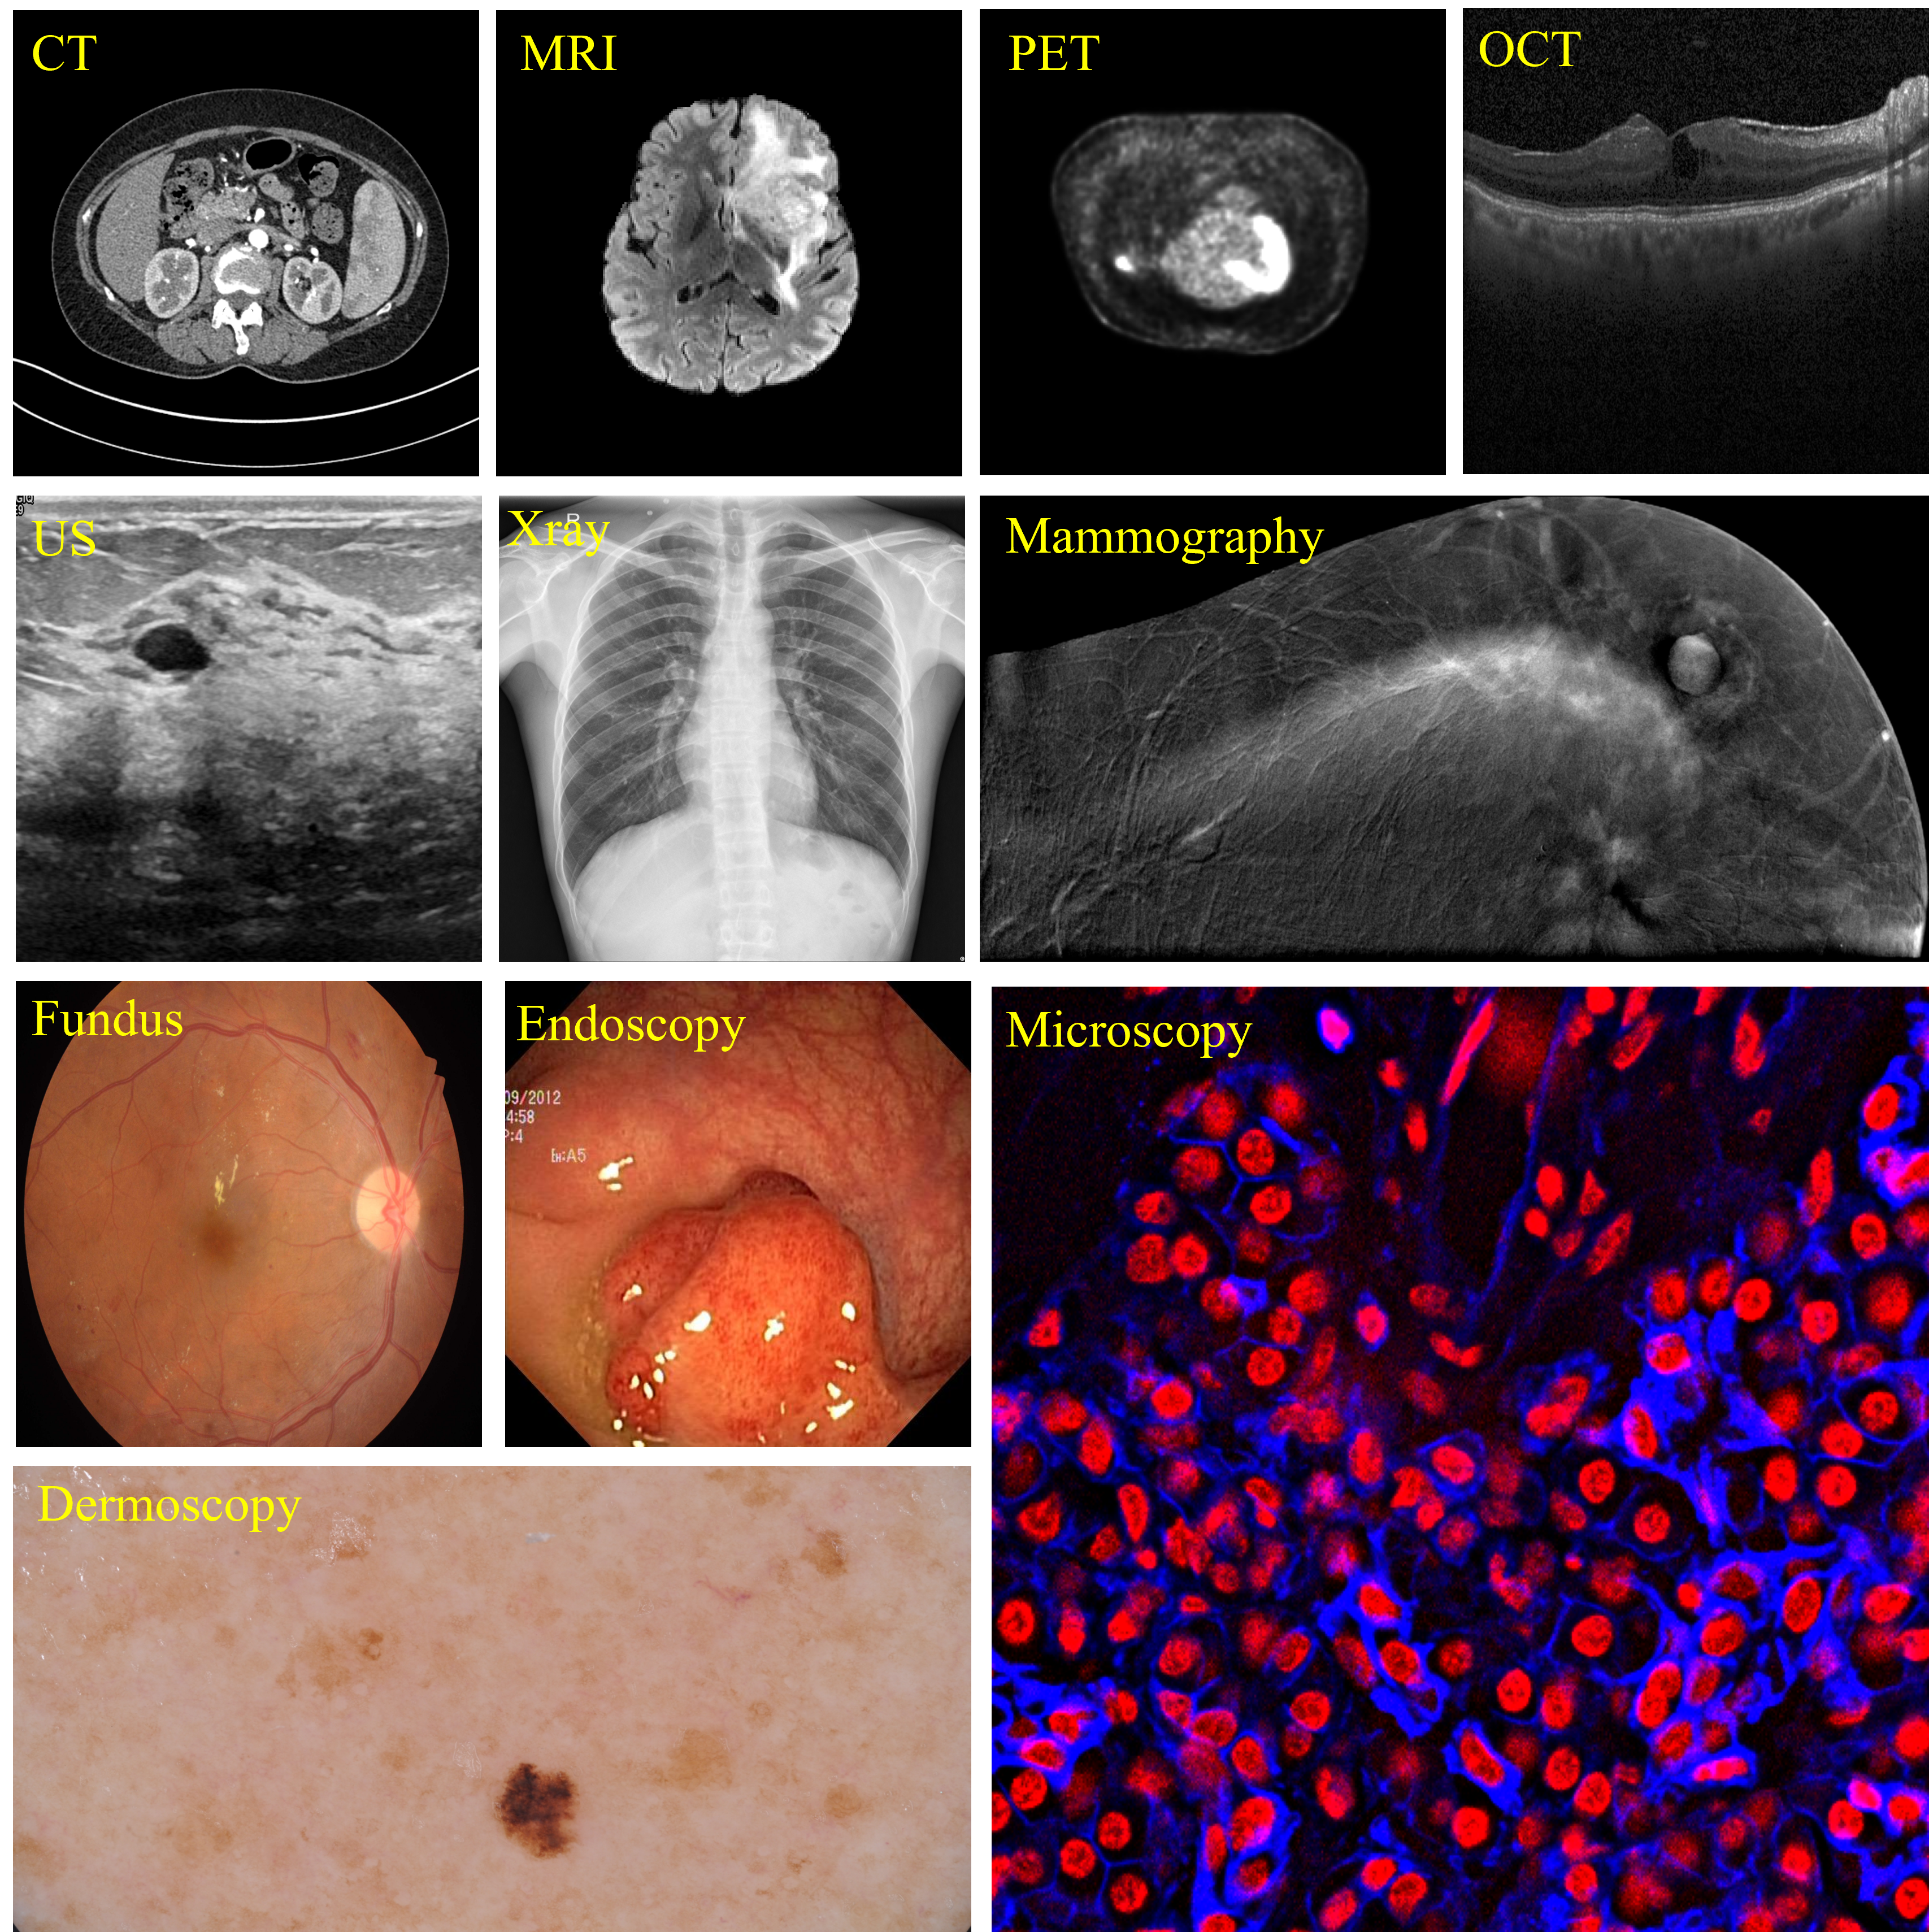

As a key task in the field of medical image analysis, medical image segmentation serves as the foundation for numerous clinical applications, such as disease diagnosis, treatment planning, and surgical interventions (Litjens et al., 2017). Accurate medical image segmentation can precisely identify anatomical structures and pathological regions, leading to more informed medical decisions. Over the last decade, deep learning-based segmentation models like nnU-Net  (Isensee et al., 2021) have achieved significant success in medical image segmentation. These models are tailored to specific imaging modalities (e.g., MRI, CT, ultrasound, as shown in Figure 1) and particular diseases (e.g., prostate tumors, pulmonary nodules). This specialization means that different scenarios require different models. Additionally, their optimization for specific datasets limits their generalization across diverse data distributions (Ma et al., 2024a). Therefore, the development of a universal model for medical segmentation becomes increasingly promising in this context, offering the potential to unify approaches across various imaging modalities and clinical applications.

Refer to caption

Figure 1: Examples of various medical imaging modalities.